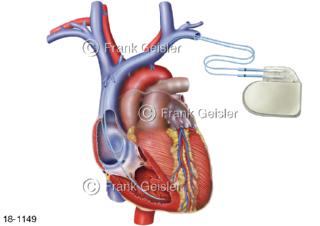

18-1149 Herzerkrankung, Herz mit Defibrillator Schockgeber beim Erkennen von Herzrhythmusstörungen